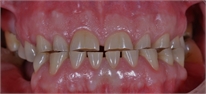

There are four types of tooth wear that we diagnose from patients’ mouths. Erosion, abrasion (I’m sorry for a missing link – I did not agree with any of the images of abrasion), abfraction and attrition. The easiest ones from these to diagnose are the erosion and attrition. You can’t go wrong with them. But it is completely different case with abfraction and abrasion.

3. Check if there are shiny facets on occluding surfaces